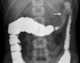

Pseudopolyps are projecting masses of scar tissue that develop from granulation tissue during the healing phase in repeated cycle of ulceration (especially in inflammatory bowel disease). Inflammatory tissue without malignant potential, pseudopolyps may represent either regenerating mucosal islands between areas of ulceration, edematous polypoid tags or granulation tissue covered by epithelium. [Source: Wikipedia ]